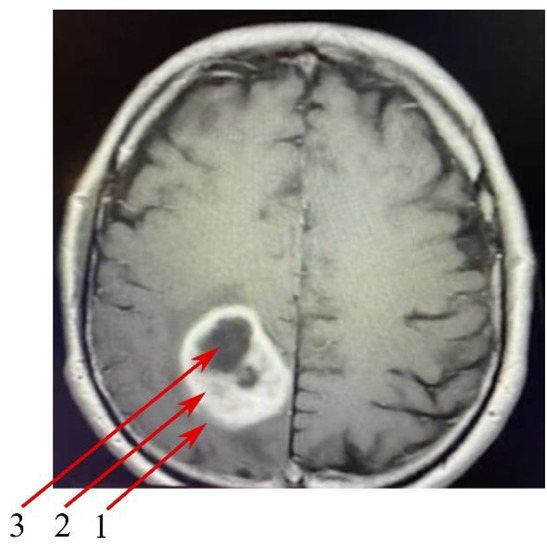

Clinical radiological morphology made it possible to distinguish three tumor zones commonly used in the literature and clinical practice (Figure 2) [22,23]:

Figure 2. Magnetic resonance imaging (MRI) scan of the brain with the glioblastoma multiforme (GBM) tumor. The image highlights the three study zones: (1) peritumoral area, (2) enhancing tumor region and (3) tumor core. Axial, T1-weighted MRI scans of a 64-year-old patient diagnosed with GBM in the right parietal lobe. The patient presented visual impairment in the left eye and visual-spatial coordination disorders, as well as a sensory impairment on the right side.

• The peritumoral area, a buffer zone between the GBM tumor and healthy tissue, with individual foci of infiltration. The peritumoral area is considered an appropriate control for the study of GBM tumors [24]. For this reason, the results obtained from GBM tumor studies were assimilated into the peritumoral area.

• The non-enhancing tumor core. This area of GBM is usually located in the central part of the GBM tumor,

• The enhancing tumor region, surrounding the tumor core.